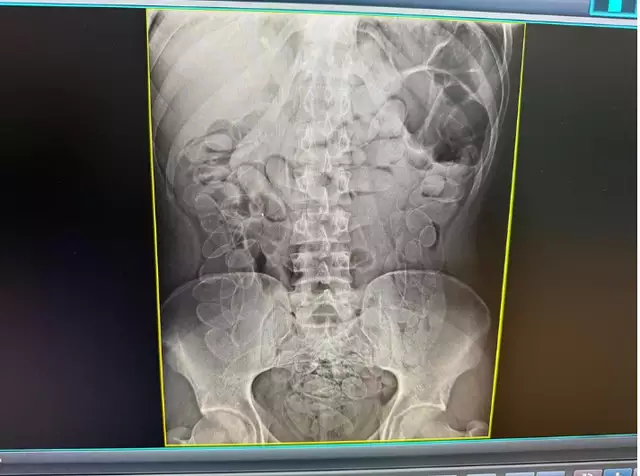

A gravidade da situação foi confirmada por um exame de raio-X abdominal, que revelou múltiplos invólucros alojados no trato digestivo da mulher.

Durante o procedimento, foram extraídas as 90 cápsulas, totalizando aproximadamente um quilo de cocaína. O material foi apreendido e entregue à Delegacia da Polícia Federal em Corumbá.